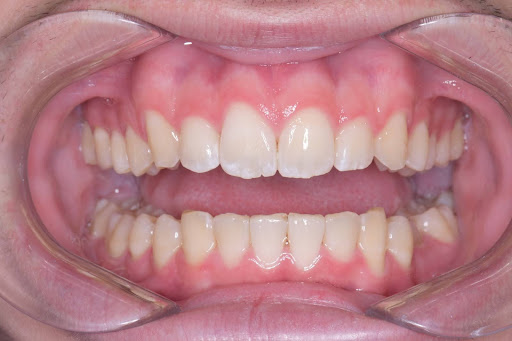

赤坂さくら歯科クリニックのインビザラインの症例写真

こちらはインビザラインのライトプランの症例写真です。

こちらは術後の写真となります。

綺麗な歯並びになっております。